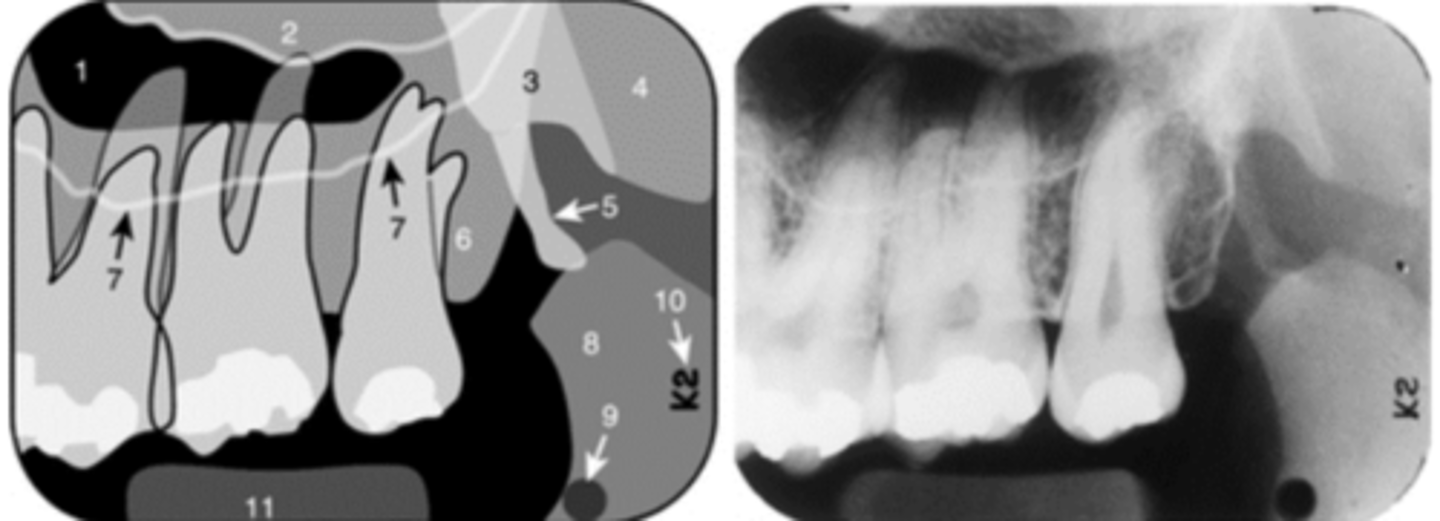

Black arrow - Nasal septum

White arrow- nasal conchae

Identify both structures

<p>Identify both structures</p>

4

New cards

nasal aperture

Identify the structure

<p>Identify the structure</p>

5

Floor of nasal cavity

Nasal cavity

In which radiolucent space does the #6 lie?

Floor of maxillary sinus

Name the curved, radiopaque line that superimposes the roots of the teeth indicated by #7.

Floor of the maxillary sinus

Name the line indicated by arrows labeled #2.

Hamulus

Name the elongated radiopacity indicated by #5.

Lateral pterygoid plate

Name the large radiopacity with a rounded inferior margin indicated by #4.

Zygoma

Name the horizontal radiopaque line labeled #2.

Name the curved line scalloping between tooth roots labeled #3.

Coronoid process

Name the curved, conical structure outlined in the bottom left corner of the image.

Lingual foramen

Name the small, radiolucent dot indicated by #4.

Lip line

Name the curved radiopacity, the superior border of which is labeled #7.